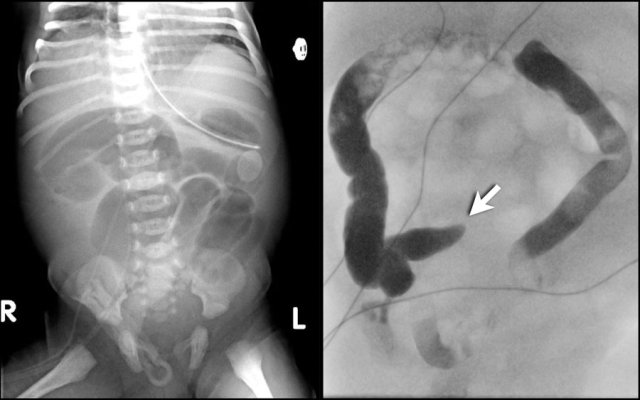

The image on the left is taken 6 days after birth and shows distended bowel with pneumatosis intestinalis.

A colon enema at 6 weeks of age shows a stricture in the colon descendens (arrow).